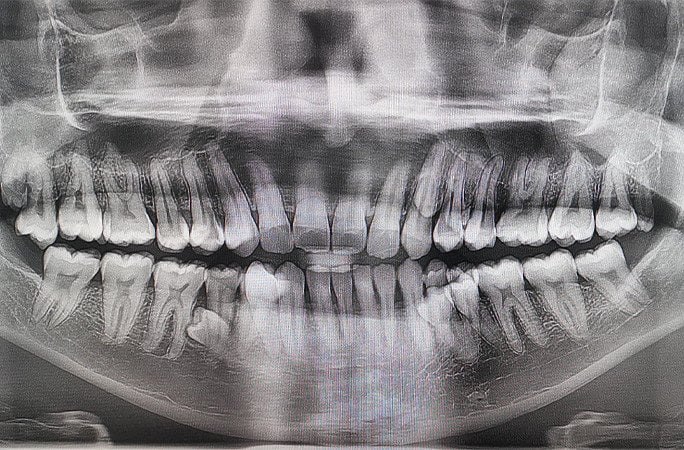

Малайзиец говорит, что долгое время даже не подозревал о своей особенности. Впервые он обратил на нее внимание в 2021 году во время семейного чаепития. По словам Пратаба, тогда он пошутил с родными, что, похоже, у него растут дополнительные зубы. Вместе они решили их сосчитать и обнаружили 38. Впоследствии рентгеновское обследование показало, что в челюсти есть еще четыре зуба, которые на тот момент не прорезались.

А недавно стоматологи, которые осматривали рот Мунианди для записи в Книгу рекордов Гиннесса, выяснили, что вскоре у него вырастет еще два зуба. Так что в будущем у малайзийца будет как минимум 44 зуба. Растут они тоже необычно, в 2 ряда, как у акулы.